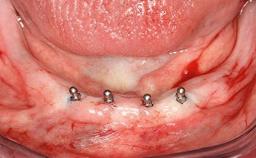

An 83-year-old man presented together with his caregiver at the dental department of the Medical University of Innsbruck, Austria with complaints of swelling in the right maxillary canine area and loss of retention of his 5-years-old mandibular denture. The patient had a significant medical history (20 years) of bipolar affective disorder with moderate depression (F 31.3) and dementia in Alzheimer’s disease (F 00.2). The patient had been in ambulant psychiatric therapy for his depressive illness for the past 20 years. He lived alone and had no children; his sister assisted with daily living. She reported that the patient exhibited compulsive hoarding behavior. In the previous two months, she had noted increasing disorientation and vertigo in the patient. She therefore accompanied him for a medical consultation at the Department of Psychiatry and Psychotherapy of the Medical University of Innsbruck. He was released home after a 6-week inpatient stay.

# of Implants 2

Type of Implants One-Piece

Defining Characteristics Fully edentulous lower jaw to be rehabilitated with two or more implants

Modality 2 interforaminal implants